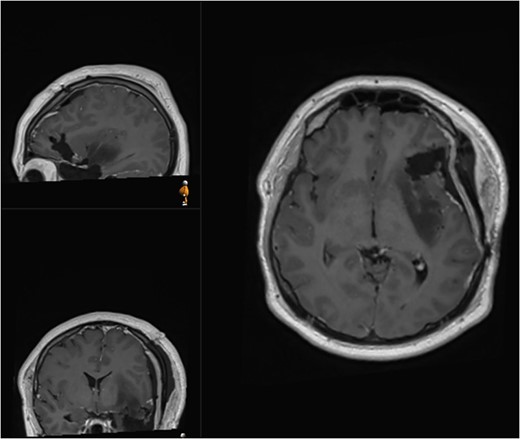

The patient was discharged at day 3 after surgery with no neurological deficits. Post-operative MRI revealed removal of the contrast enhancing portion of the tumour and intentional residual tumour at the posterior margin of the insula (Fig. 4). Histology analysis revealed malignant transformation with IDH-mutant anaplastic astrocytoma, with malignant transformation (84% MGMT methylated, ATRX mutant, p53 overexpressed >90), WHO grade 3. The patient proceeded with oncological treatment in the form of chemotherapy and radiotherapy.

Postoperative (second surgery) MRI demonstrating residual tumour at the posterior margin of the insula.